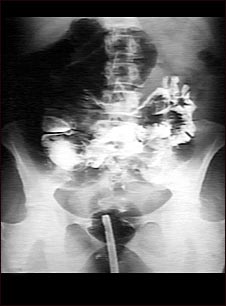

Radiografía de vólvulo

Serie GI en un paciente con torsión intestinal (vólvulo).